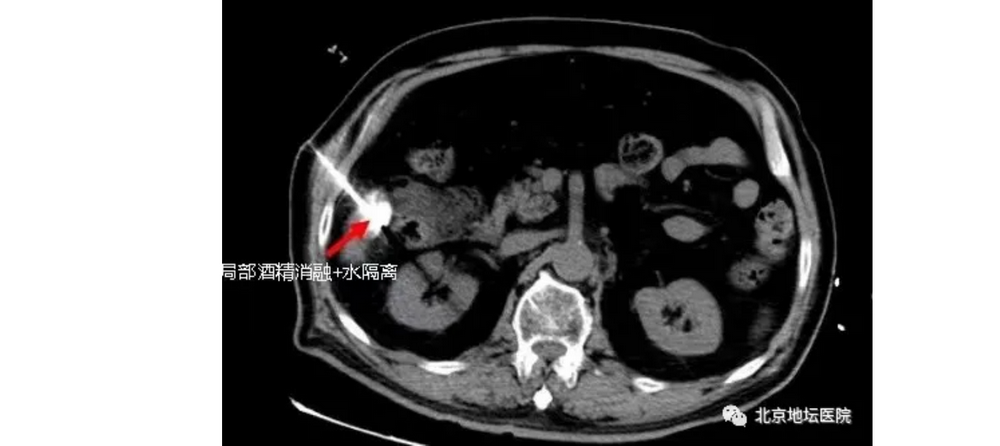

在CT引导下,孙巍仔细迅速地将引导针插入,在肿瘤的位置注入无水酒精和造影剂的混合物。很快,酒精均匀扩散到整个肿瘤内。而肿瘤的轮廓也在造影剂的作用下更清晰的显现,方便下一步的射频消融。

所以,孙巍在进行消融手术前,还进行了一步对手术十分关键的操作——局部水隔离!

所谓水隔离,就是在王大爷肝脏与升结肠间注入一定量的水,保护肠道不受损害。因为用水较高的压力,可以把肠管和肝脏上的肿瘤隔离开来,使消融所产生的热量不会危害到升结肠。

水隔离是目前在消融手术中非常有用的一个办法,它能保证摧毁肿瘤的同时,而不伤及正常的组织,达到手术安全的目的。